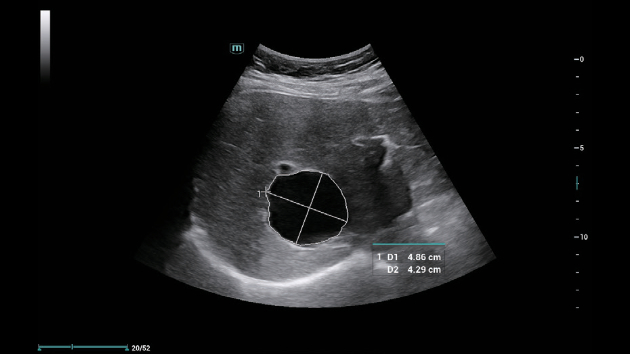

Mindray Consona N6 Smart Calc — интеллектуальная программа для автоматического расчета биометрических параметров в реальном времени.

Smart Calc — интеллектуальная программа для автоматической трассировки, измерения и расчета биометрических параметров в реальном времени. Принцип работы основан на алгоритмах машинного обучения, которые анализируют ультразвуковые данные, распознают анатомические структуры и автоматически определяют границы объектов (например, фолликулов, толщины комплекса интима-медиа). Настраиваемые параметры включают выбор протоколов (акушерство, кардиология), коррекцию глубины сканирования и калибровку под индивидуальные клинические задачи. Скорость обработки данных достигается за счет интеграции с платформой ZST+, которая обеспечивает 10-кратное ускорение формирования изображений. Автоматизация расчетов (например, объема фолликулов в режиме Smart FLC 3D) сокращает время исследования на 40%, позволяя принять на 5-7 пациентов больше за смену.

Mindray Consona N6 Smart Calc — интеллектуальная программа для автоматического расчета биометрических параметров в реальном времени

Smart Calc — интеллектуальная программа для автоматической трассировки, измерения и расчета биометрических параметров в реальном времени. Принцип работы основан на алгоритмах машинного обучения, которые анализируют ультразвуковые данные, распознают анатомические структуры и автоматически определяют границы объектов (например, фолликулов, толщины комплекса интима-медиа). Настраиваемые параметры включают выбор протоколов (акушерство, кардиология), коррекцию глубины сканирования и калибровку под индивидуальные клинические задачи. Скорость обработки данных достигается за счет интеграции с платформой ZST+, которая обеспечивает 10-кратное ускорение формирования изображений. Автоматизация расчетов (например, объема фолликулов в режиме Smart FLC 3D) сокращает время исследования на 40%, позволяя принять на 5-7 пациентов больше за смену.